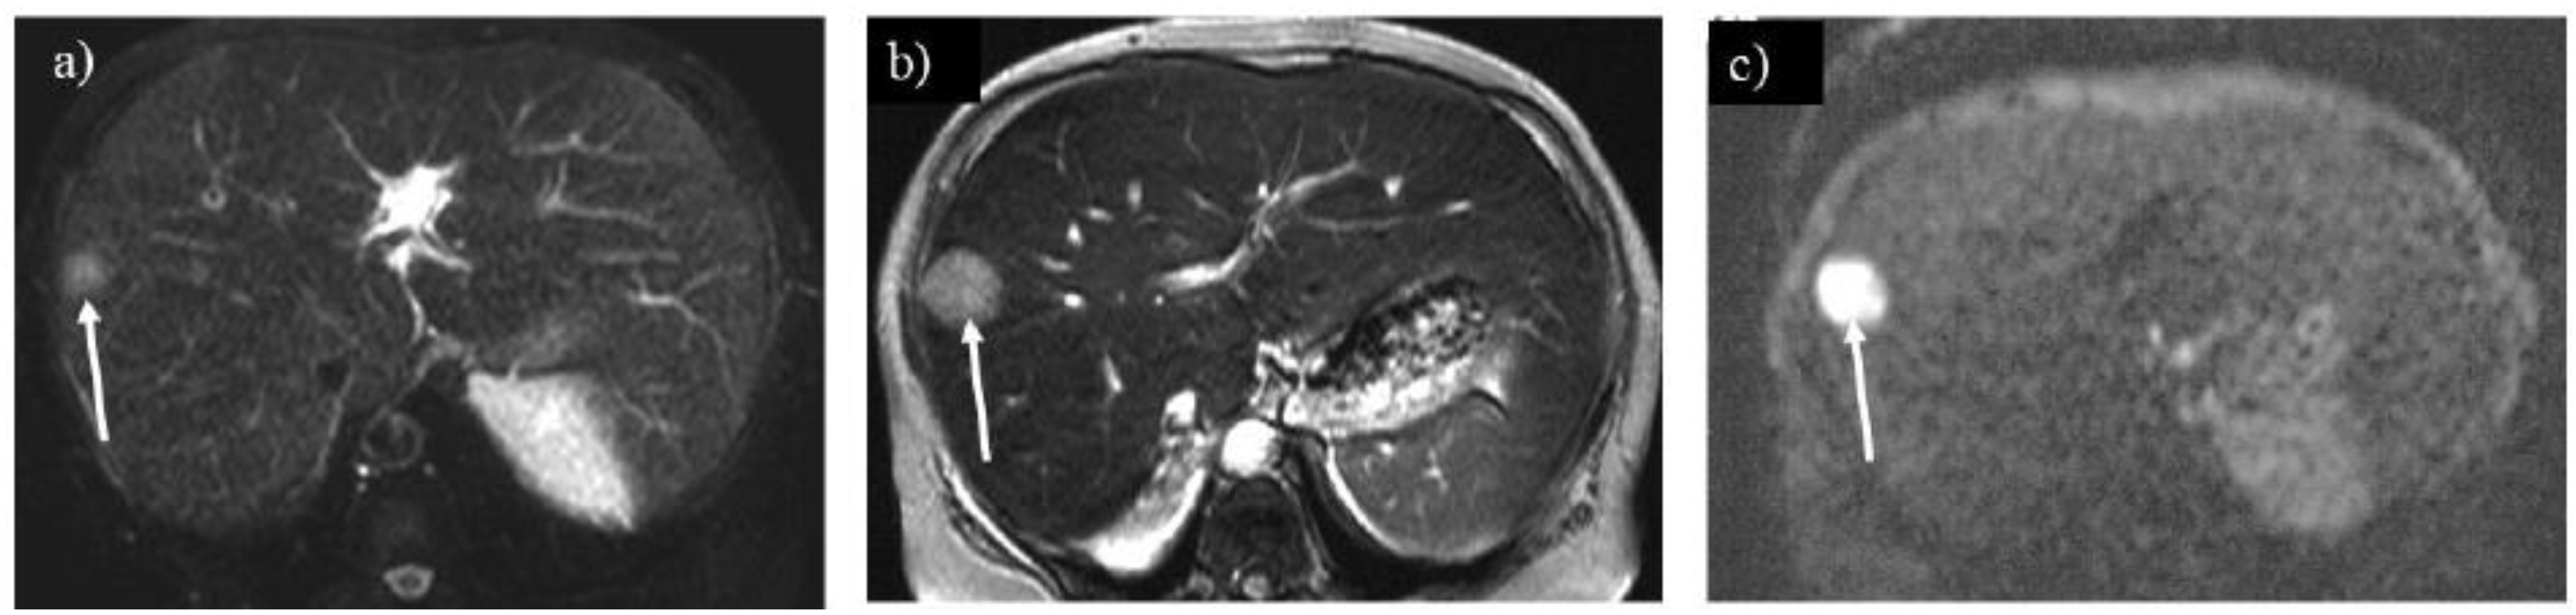

Figure 8. A liver tumor shows high intensity on T2-weighted imaging (A) in a 55-year-old woman with glycogen storage disease type Ia (arrow). The tumor grew rapidly over 1 year (B, arrow). The tumor shows marked hyperintensity on diffusion-weighted imaging (C, arrow), which is pathologically proven to be a hepatocellular carcinoma.

Hepatic adenoma and adenomatosis are common complications of GSDs [1,2,3,6,7,8]. Some genetic alternation may contribute to a larger hepatic adenoma in patients with GSD type Ia [3]. Different from hepatic adenomas without GSDs, those associated with GSDs are often found in male patients and multiple lesions (i.e., hepatic adenomatosis) and increase in size (Figures 3B, C, 7B and C) [17,18]. The hepatic adenoma associated with GSDs are not related to contraceptives. It is clinically problematic to differentiate between a growing hepatic adenoma and hepatocellular carcinoma. Indeed, hepatic adenoma can transform into hepatocellular carcinoma in the older patients with GSDs, exhibiting similar imaging appearances in GSDs (Figures 3C, 7B and 8) [9,17]. Multimodality imaging surveillance should be performed once a hepatic tumor presenting strong enhancement in the arterial phase is identified in patients with GSDs [6,9].